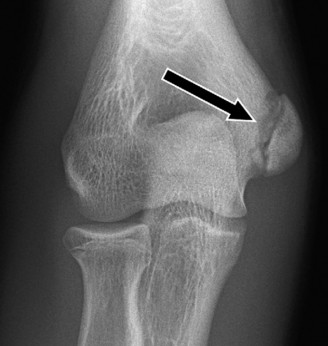

Imaging should include x-rays, which may demonstrate posterior glenoid bone loss or an impaction fracture on the anterior-superior humeral head (Fig. 2–38). CT images with 3D reconstructions can be very useful when assessing the extent of glenoid bone loss and evaluating glenoid and humeral version. Normal glenoid version is from −2 to −8 degrees of retroversion, and this may be increased in posterior instability. MRI can also be useful when assessing the posterior labrum (Fig. 2–39).

Figure 2–38 Radiographs showing a posterior shoulder dislocation.